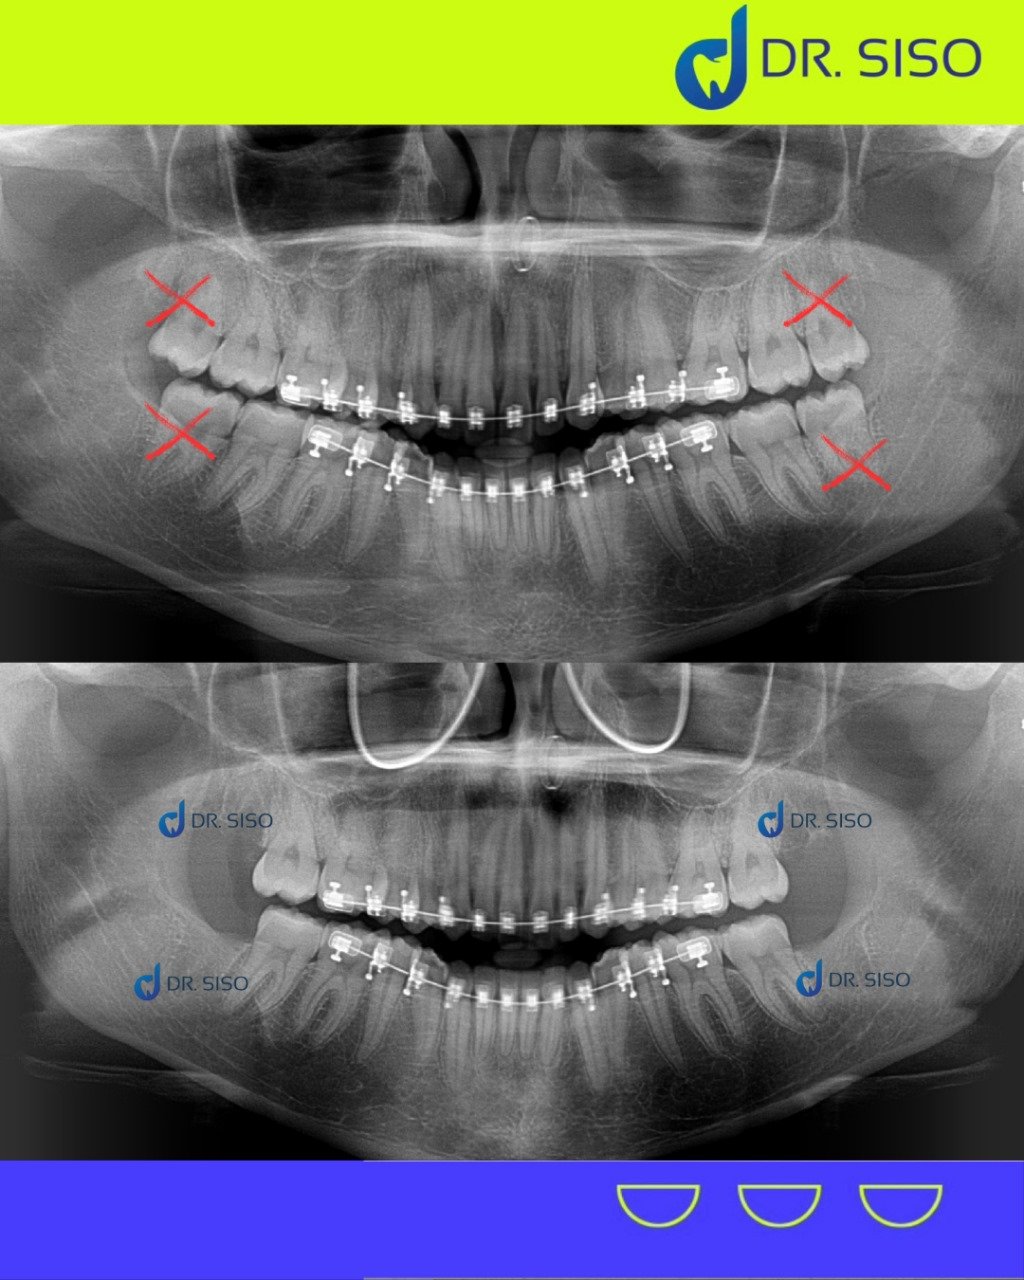

Aquele incômodo no fundo da boca pode ser causado pelos sisos! Quando não há espaço suficiente para nascerem corretamente, eles podem provocar dor, inchaço e até infecções. A extração do siso é um procedimento seguro que evita problemas futuros e alivia o desconforto.

Sim, em muitos casos. Mesmo sem dor, o siso pode estar mal posicionado, pressionando outros dentes, causando reabsorção óssea ou prejudicando a mordida. A avaliação clínica e radiográfica é essencial para decidir com segurança.

Sim! É comum extrair até os quatro sisos em um único procedimento, especialmente quando o paciente quer otimizar a recuperação e evitar múltiplas cirurgias.